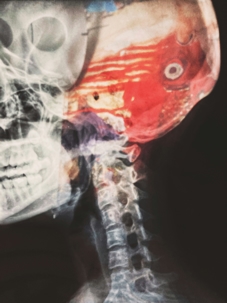

Importance of Diagnosis and Documentation

Ensure your doctor uses CT scans, MRIs, and other diagnostic tools to examine the injury thoroughly. Proper documentation of the extent of the brain damage helps you in court when proving the severity of your TBI. Without these medical records, building a solid case is much more complicated.